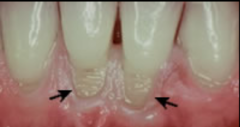

external resorption

Front

-unknown etiology -braces

Back